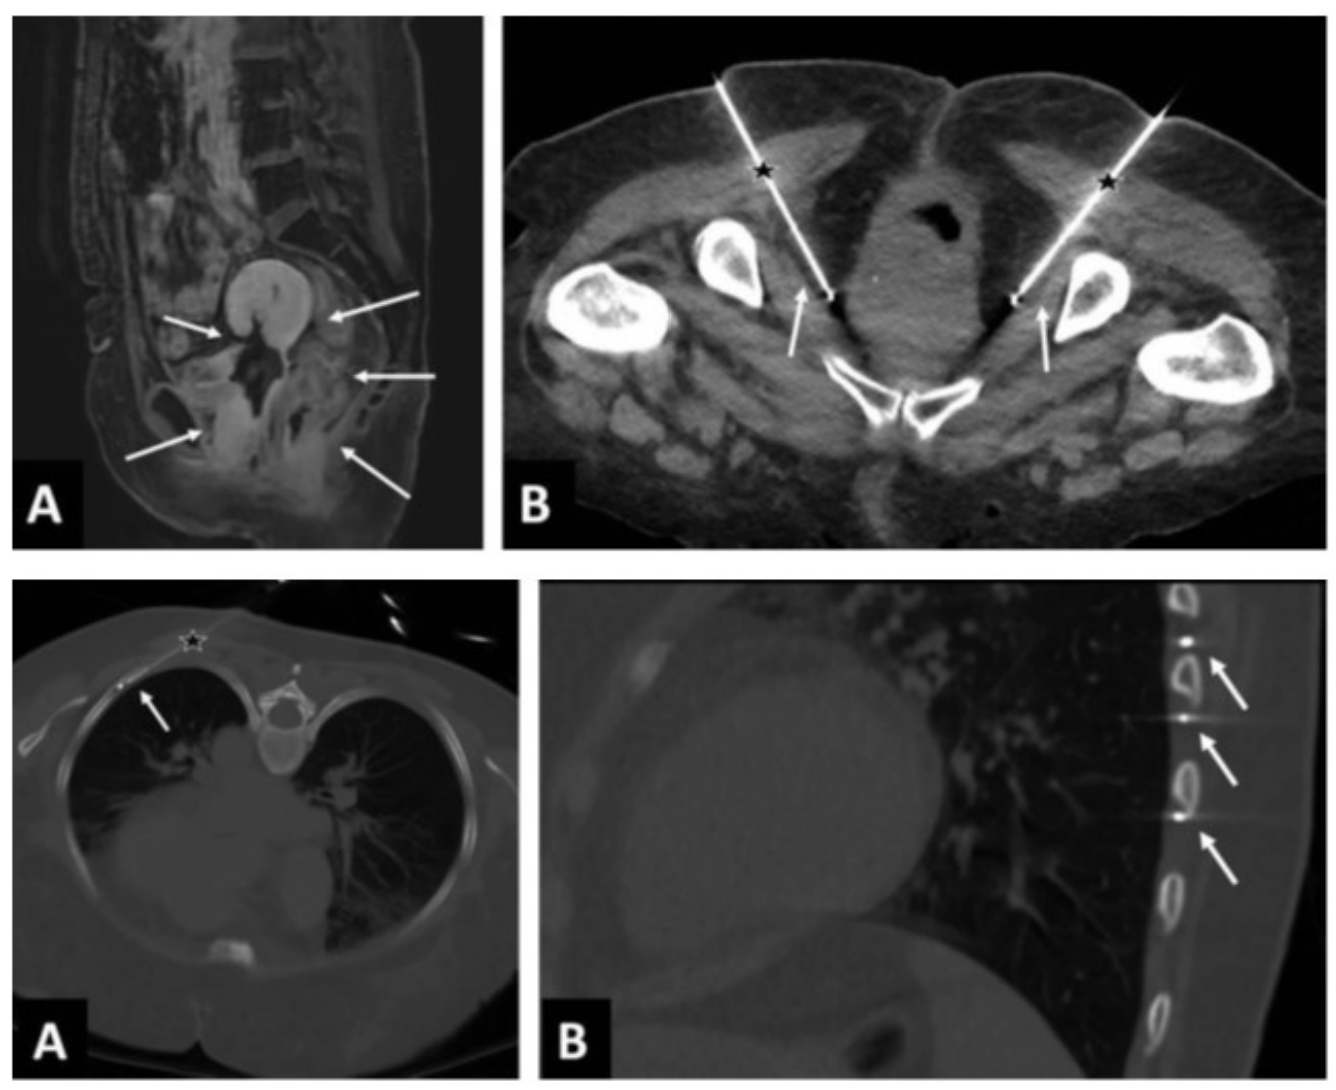

Криоанальгезия межреберных нервов

• N=18. Интенсивность боли: 7.5 баллов исходная, 1,2 после процедуры и 4.1 балла через 51 день. W. Moore, D. Kolnick, J. Tan, H.S. Yu. CT guided percutaneous cryoneurolysis for post thoracotomy pain syndrome: early experience and effectiveness. Acad Radiol. 2010 May;17(5):603-6.

• N=43 (ретроспективное). 60% значимое снижение боли после процедуры, 50% значимое снижение боли через 3 мес. Не было невром, невритов и только 3 случая пневмоторакса.

C.R Green, A.M. de Rosayro, A.R. Tait. The role of cryoanalgesia for chronic thoracic pain: results of a long-term follow up. J Natl Med Assoc. 2002 Aug;94(8):716-20.

Лечение онкологической боли

• N=5. Интенсивность боли у пациентов с раком ПЖ снизилась с 9.4 ВАШ до 2.6, 2.6 и 3 через 1, 3 и 6 мес.

• D. Filippiadis, N. Ptohis, E. Efthymiou, A. Kelekis. A Technical Report on the Performance of Percutaneous Cryoneurolysis of Splanchnic Nerves for the Treatment of Refractory Abdominal Pain in Patients with Pancreatic Cancer: Initial Experience. Cardiovasc Intervent Radiol (2021) 44:789-794.

Криоанальгезия при онкологической боли

• D. Filippiadis, E. Efthymioua, A. Tsochatzisa et al. Percutaneous cryoanalgesia for pain palliation: Current status and future trends. Diagnostic and Interventional Imaging 102 (2021) 273-278